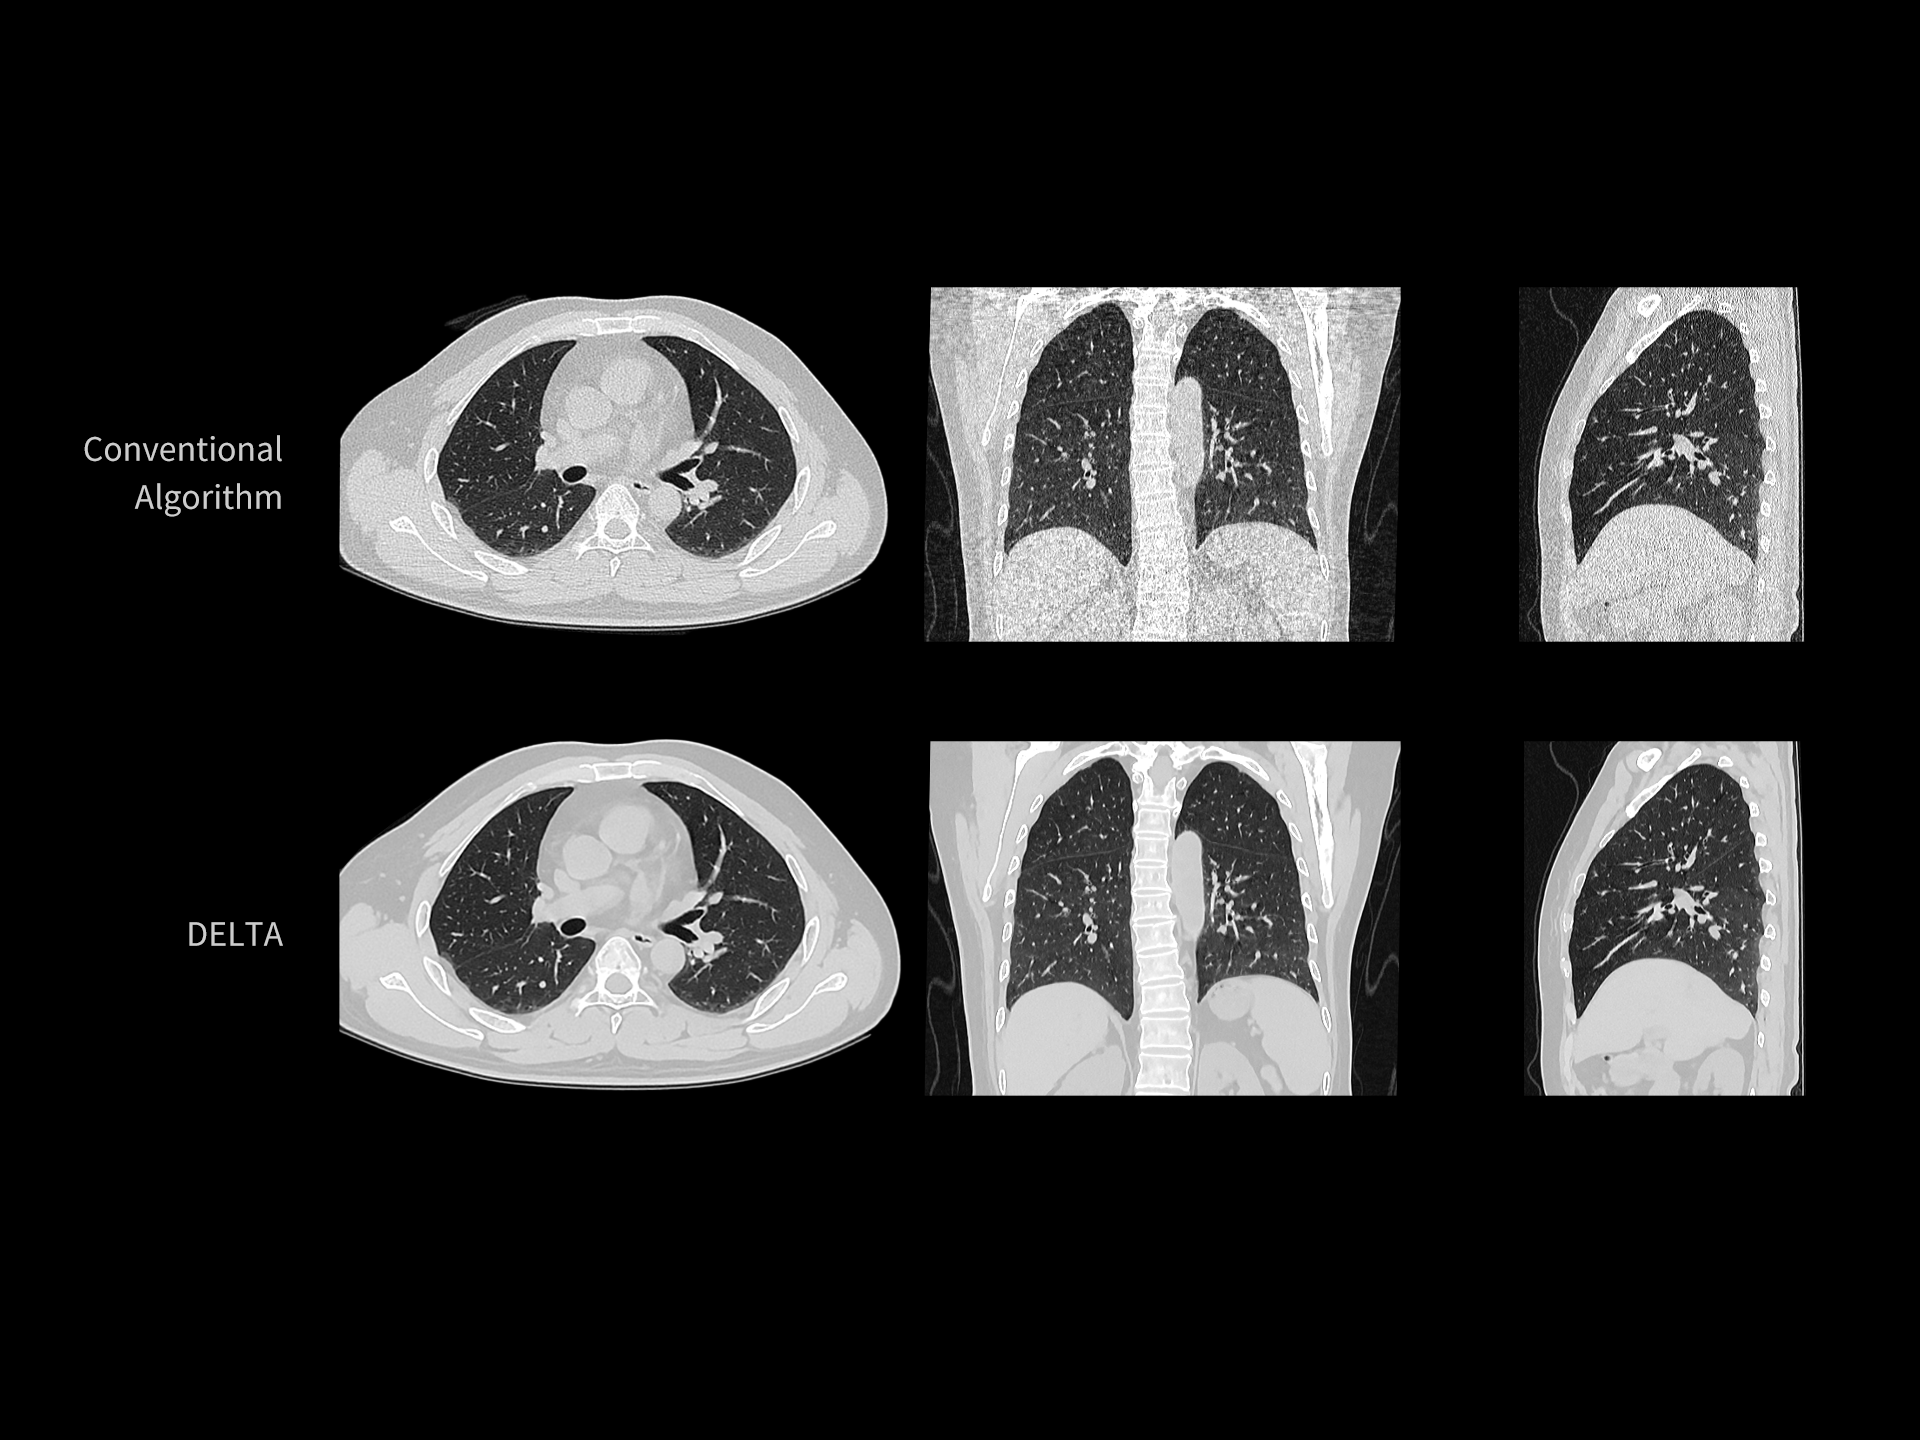

DELTA îmbunătățește vizualizarea texturii pulmonare în scanările cu doză redusă

| Parametri scanare |

kV: 120 mAs: 10 Lungime scanare: 277 mm CTDIvol: 0.9 mGy Doză efectivă: 0.4 mSv |

| Parametri reconstrucție |

Matrice: 512 × 512 Grosime secțiune: 1.0 × 0.8 mm HIR: B_SOFT_B Nivel DL-Denoise: 3 WW/WL: 1400 / -400 |

| Contrast | — |